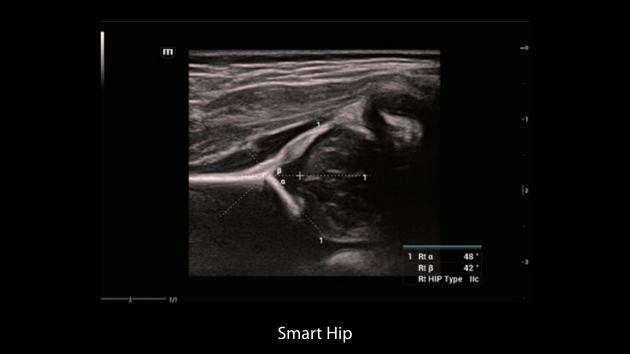

El sistema Nuewa I9, dise?ado exclusivamente para la atenciĂłn mĂ©dica neonatal y de mujeres, brinda una experiencia innovadora integral. Estas innovaciones se desarrollan sobre la base de un conocimiento profundo de situaciones clĂnicas complejas para proporcionar respuestas precisas y oportunas, una gran eficiencia y una experiencia de usuario extraordinaria.

La plataforma ZST+?es una innovaciĂłn extraordinaria que representa toda una evoluciĂłn en el ĂĄmbito de la ecografĂa. Transforma las mĂ©tricas ecogrĂĄficas de la formaciĂłn de haces convencional al procesamiento basado en datos de canal. Supera la limitaciĂłn tradicional de tener que equilibrar entre resoluciĂłn espacial, resoluciĂłn temporal y uniformidad del tejido, con lo que ofrece una calidad de imagen excepcional para soluciones de producciĂłn de imĂĄgenes infinitas con mejoras continuas.